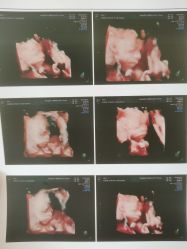

• 杭州贝瑞斯美华妇儿医院·早孕·产检·儿科

肚里圆圆 上传于 21-07-07 | 报错

夜空中的游鱼 上传于 21-07-06 | 报错